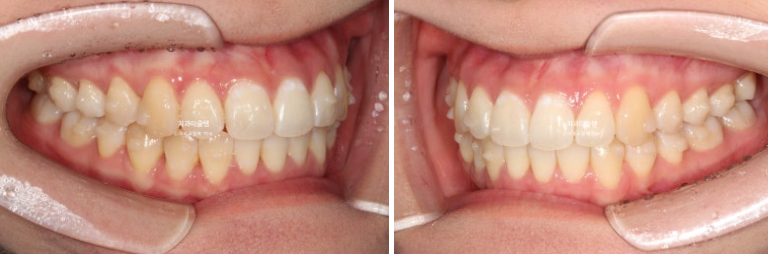

개선된 덧니와 가위교합

24.02~25.10